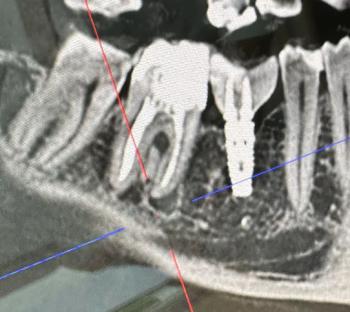

Bone Loss Around Front Teeth With Braces X-Ray Case

Bone Loss Around Front Teeth With Braces X-Ray Case Analysis

What Is Seen in This Case

The X-ray image shows the lower front teeth with orthodontic braces in place. The tooth roots are visible, but the bone level around the roots appears reduced and uneven. There are darker areas between and around the roots, suggesting loss of supporting bone rather than healthy, dense bone.

This finding is especially important in patients undergoing orthodontic treatment.

Professional Comment